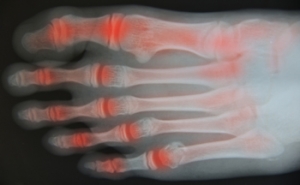

Arthritis in the Toes

Arthritis can occur in any part of the body where joints exist. Since toes have many joints, this is a common place for arthritis to develop. Different types of arthritis can attack the toes, primarily osteoarthritis, rheumatoid arthritis, and gout. If the cartilage wears away between the bones in the toes, they will rub together and inflammation will occur. The big toe is the one most often affected. Past injuries, such as broken or sprained toes, can gradually cause arthritis. Aging, being overweight, and having a family history of arthritis are risk factors for this affliction. Symptoms of toe arthritis include pain, stiffness, and swelling. A clicking, popping, or a grinding noise can also be symptoms. Toe arthritis can cause difficulty with mobility. If you have toe pain, it is suggested that you consult with a podiatrist who can properly diagnose arthritis, and provide correct treatment options.

Arthritic Foot Care

Arthritis is a term that is commonly used to describe joint pain. The condition itself can occur to anyone of any age, race, or gender, and there are over 100 types of it. Nevertheless, arthritis is more commonly found in women compared to men, and it is also more prevalent in those who are overweight. The causes of arthritis vary depending on which type of arthritis you have. Osteoarthritis for example, is often caused by injury, while rheumatoid arthritis is caused by a misdirected immune system.

Symptoms

- Swelling

- Pain

- Stiffness

- Decreased Range of Motion

Arthritic symptoms range in severity, and they may come and go. Some symptoms stay the same for several years but could potentially get worse with time. Severe cases of arthritis can prevent its sufferers from performing daily activities and make walking difficult.

Risk Factors

- Occupation – Occupations requiring repetitive knee movements have been linked to osteoarthritis

- Obesity – Excess weight can contribute to osteoarthritis development

- Infection – Microbial agents can infect the joints and trigger arthritis

- Joint Injuries – Damage to joints may lead to osteoarthritis

- Age – Risk increases with age

- Gender –Most types are more common in women

- Genetics – Arthritis can be hereditary

If you suspect your arthritis is affecting your feet, it is crucial that you see a podiatrist immediately. Your doctor will be able to address your specific case and help you decide which treatment method is best for you.